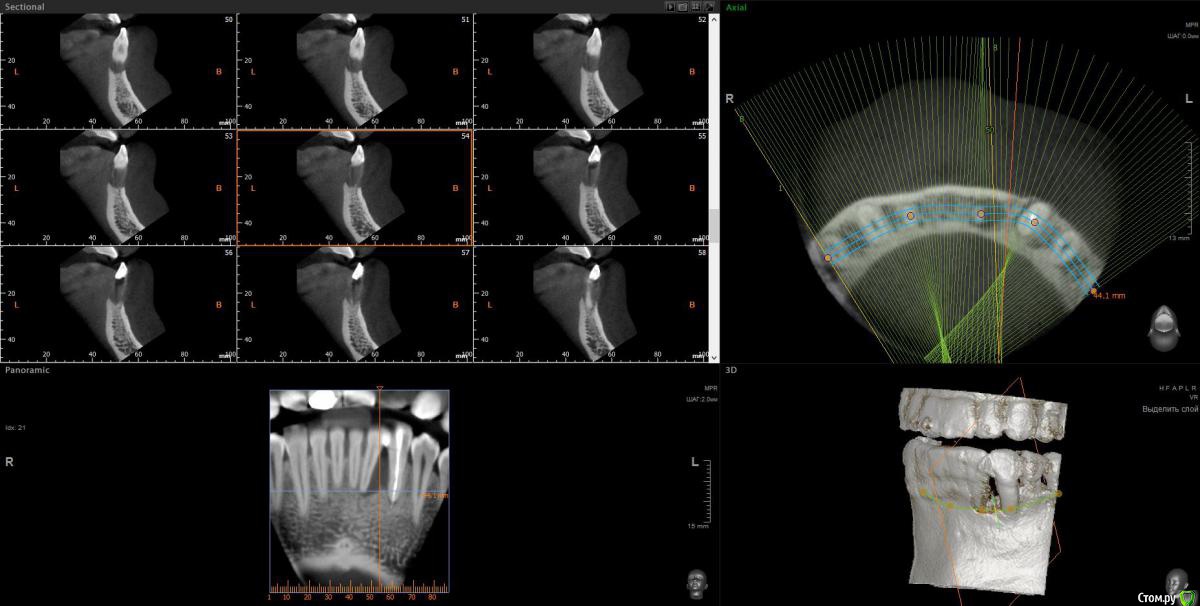

wladdX Опубликовано 3 февраля, 2017 Поделиться Опубликовано 3 февраля, 2017 Пациент 37 лет. 2,5 года назад в другом лечебном учреждении оперировали, по представленной ксерокопии карты, пародонтальную кисту. Прежних Rg-грамм нет.Сейчас следующая картина: Зубы 32 и 33 удаляем, а как далее правильно поступить?Каким способом лучше возместить дефект кости? Ваше мнение, коллеги? Ссылка на комментарий

wladdX Опубликовано 6 февраля, 2017 Автор Поделиться Опубликовано 6 февраля, 2017 Боюсь, что ничего из предложенного выше не выйдет. Вестибулярная и язычная стенки альвеол отсутствуют почти полностью. Зубы подвижны, почти постоянное гноетечение из карманов. Ссылка на комментарий

Доктор Добрых Дел Опубликовано 6 февраля, 2017 Поделиться Опубликовано 6 февраля, 2017 Сетка или цитопласт. Главное чтоб костные пики были медиально и дистально. Предварительно основательно пролечить парадонтит Ссылка на комментарий

Д-р Доктор Опубликовано 6 февраля, 2017 Поделиться Опубликовано 6 февраля, 2017 Ксено и аутографт 50\50, цитопласт, перекрыть сст. Ссылка на комментарий

wladdX Опубликовано 6 февраля, 2017 Автор Поделиться Опубликовано 6 февраля, 2017 (изменено) Тоже склоняюсь либо к сетке либо к "sausage".Плохо, что есть гноетечение, из-за этого опасаюсь делать сразу после удаления. Изменено 6 февраля, 2017 пользователем wladdX Ссылка на комментарий